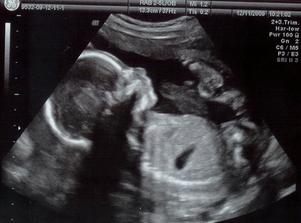

Tánička 26.4.2010 13:12 3110g 49cm

Tánička se nám narodila na rozdíl od Hynečka přirozeně 26.4.2010 (40+1) v Podolí, celkem rychle. Přes noc začaly kontrakce, ráno už byly po 5 minutách a ve 13:12 uz byla na světě. Bylo překvapením, že je to holčička, počítali jsme spíš s Adámkem (můj antiinstinkt opět zabodoval 🙂) a až pár minut po porodu jsme definitivně rozhodli jméno 😀 Co se týče sání, tak to se pobratřila a ještě ten den blinkala moje mlezivo.